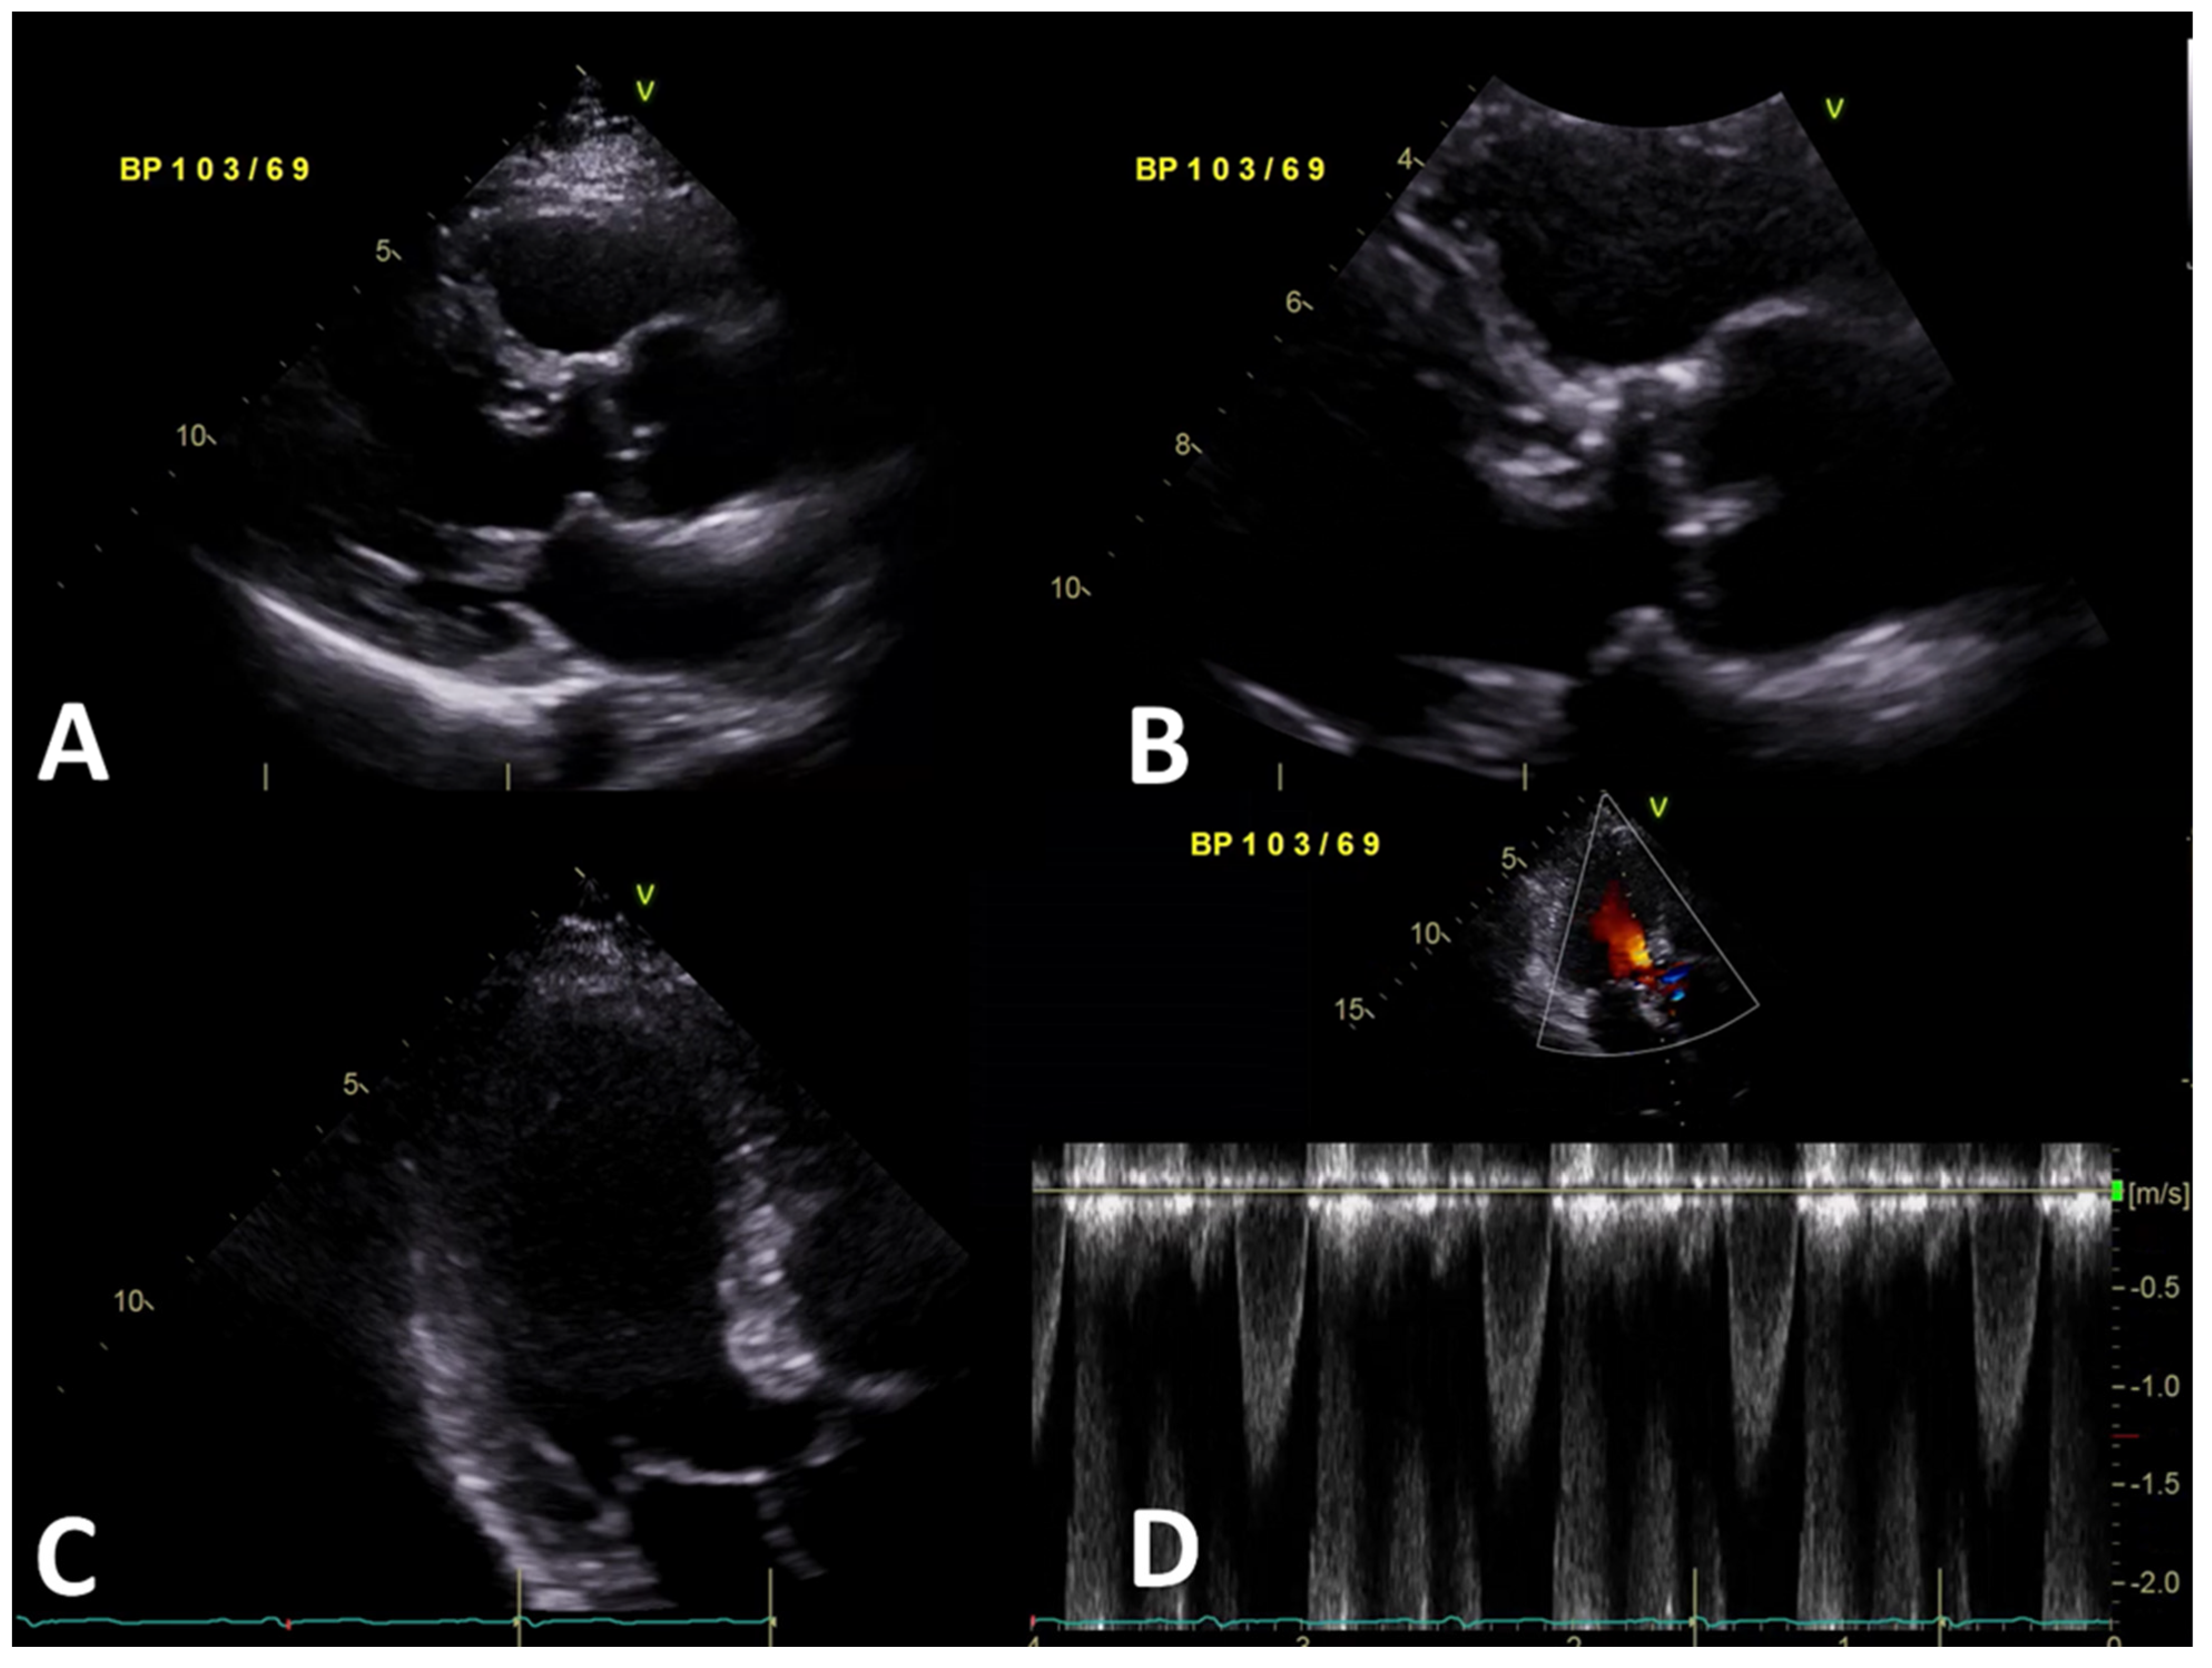

2. Case Presentation